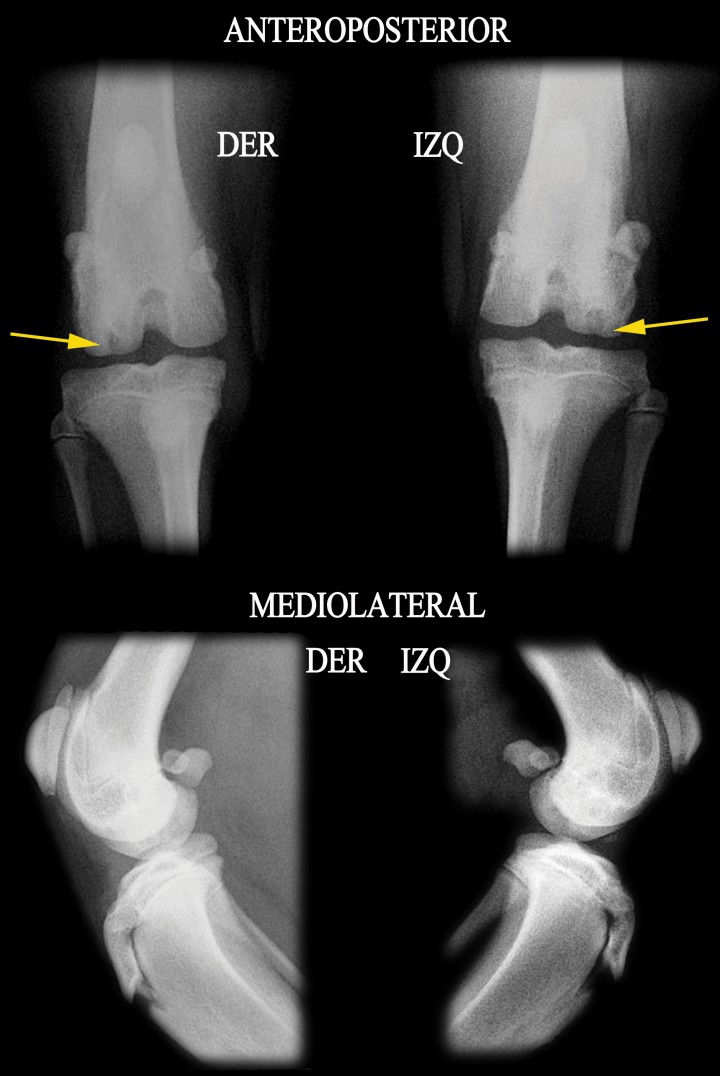

El examen radiológico realizado bajo sedación (utilizando la combinación de dexmedetomidina 5 µg/kg, butorfanol 0,3 mg/kg en inyección intramuscular) consistió en proyecciones anteroposteriores y mediolaterales de ambas extremidades posteriores. En dichas proyecciones se pudo apreciar un área de radiolucidez bilateral en la zona lateral del cóndilo femoral lateral de ambas rodillas (Fig. 2). Dichas áreas de radiolucidez se encontraban rodeadas de una zona de esclerosis subcondral perilesional. Estos hallazgos radiológicos eran compatibles con una OCD bilateral de rodilla.

<p>Detalle de las radiografías anteroposterior y mediolateral, donde se muestra la lesión (flechas amarillas) (DER: Derecha, IZQ: Izquierda).</p>

Detalle de las radiografías anteroposterior y mediolateral, donde se muestra la lesión (flechas amarillas) (DER: Derecha, IZQ: Izquierda).